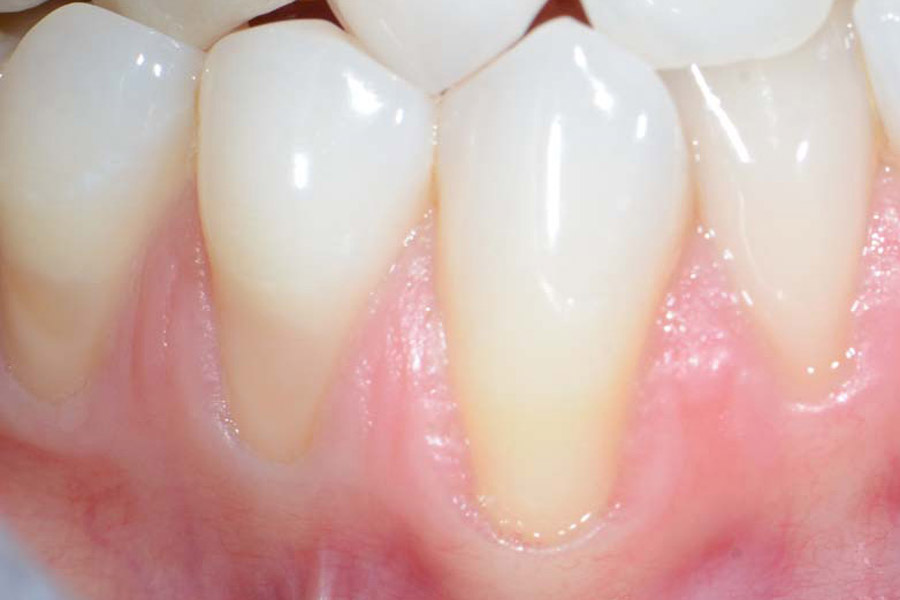

La recessione gengivale è una condizione in cui il margine della gengiva si ritira, esponendo la radice del dente. Questo problema, noto anche come gengive ritirate o gengive retratte, può iniziare in età giovanile e manifestarsi in modo più evidente dopo i 40 anni.

Oltre a compromettere l’estetica del sorriso, causando l’impressione di avere denti più lunghi e dal colore non uniforme, la recessione gengivale può portare a sensibilità dentale e aumentare il rischio di altre patologie. Una delle cause più comuni è uno spazzolamento scorretto e troppo energico, spesso eseguito con spazzolini a setole dure.

Sintomi delle gengive ritirate

I segnali che indicano la presenza di una recessione gengivale sono spesso chiari. Riconoscerli è il primo passo per intervenire tempestivamente.

I sintomi e i segni clinici più comuni includono:

- Gengive visibilmente ritirate

- Denti che appaiono più lunghi del normale

- Aumentata sensibilità dentale al caldo e al freddo

Si ricorre alla chirurgia quando la recessione gengivale causa problemi estetici significativi, ipersensibilità, difficoltà di pulizia o precede un trattamento ortodontico. L’obiettivo è ricoprire la radice esposta con un innesto di tessuto. Le moderne tecniche microchirurgiche sono mini-invasive e permettono di trattare più denti in una sola seduta con un disagio post-operatorio minimo.